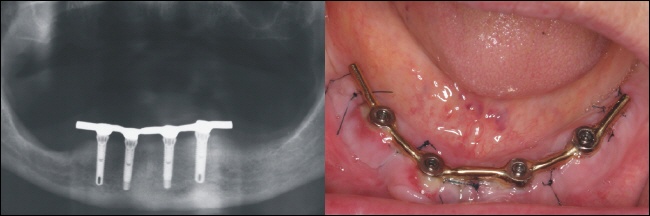

Versorgung

Im zahntechnischen Labor ist innerhalb von einem Tag mit vorgefertigten Teilen (konfektionierten Teilen) ein Steg hergestellt worden, der einen Tag nach der Implantation auf die Implantate aufgeschraubt wird. Die Röntgenkontrolle (links) zeigt den exakten Sitz des Steges auf den Implantaten.

Im Mund zeigt sich eine dezente Schwellung der Schleimhaut um die eingeschraubte Stegkonstruktion (rechts im Bild).